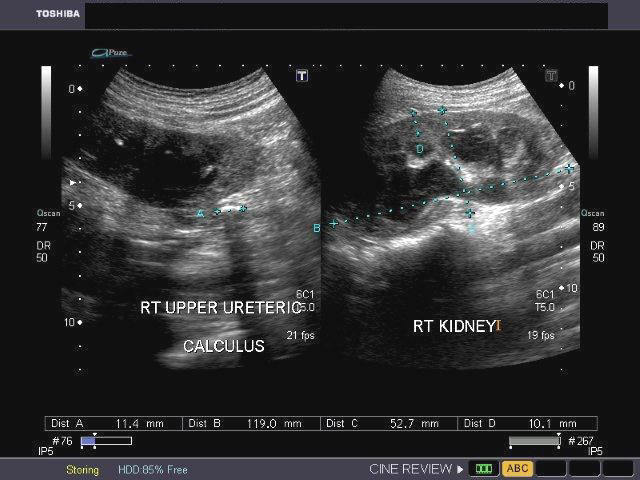

Case-2: Pyonephrosis with ureteric calculus

Ultrasound images of the right kidney show fluid-debris levels in the calyces as well as the pelvis of the right kidney. The pelvicalyces show moderate dilatation. There is also evidence of right hydroureter extending down to the lower third. Here a right ureteric calculus is seen (1.1 cms. in size). Final diagnosis- right pyonephrosis caused by right ureteric calculus. Ultrasound images are courtesy of Dr. Ravi Kadasne, MD, UAE.